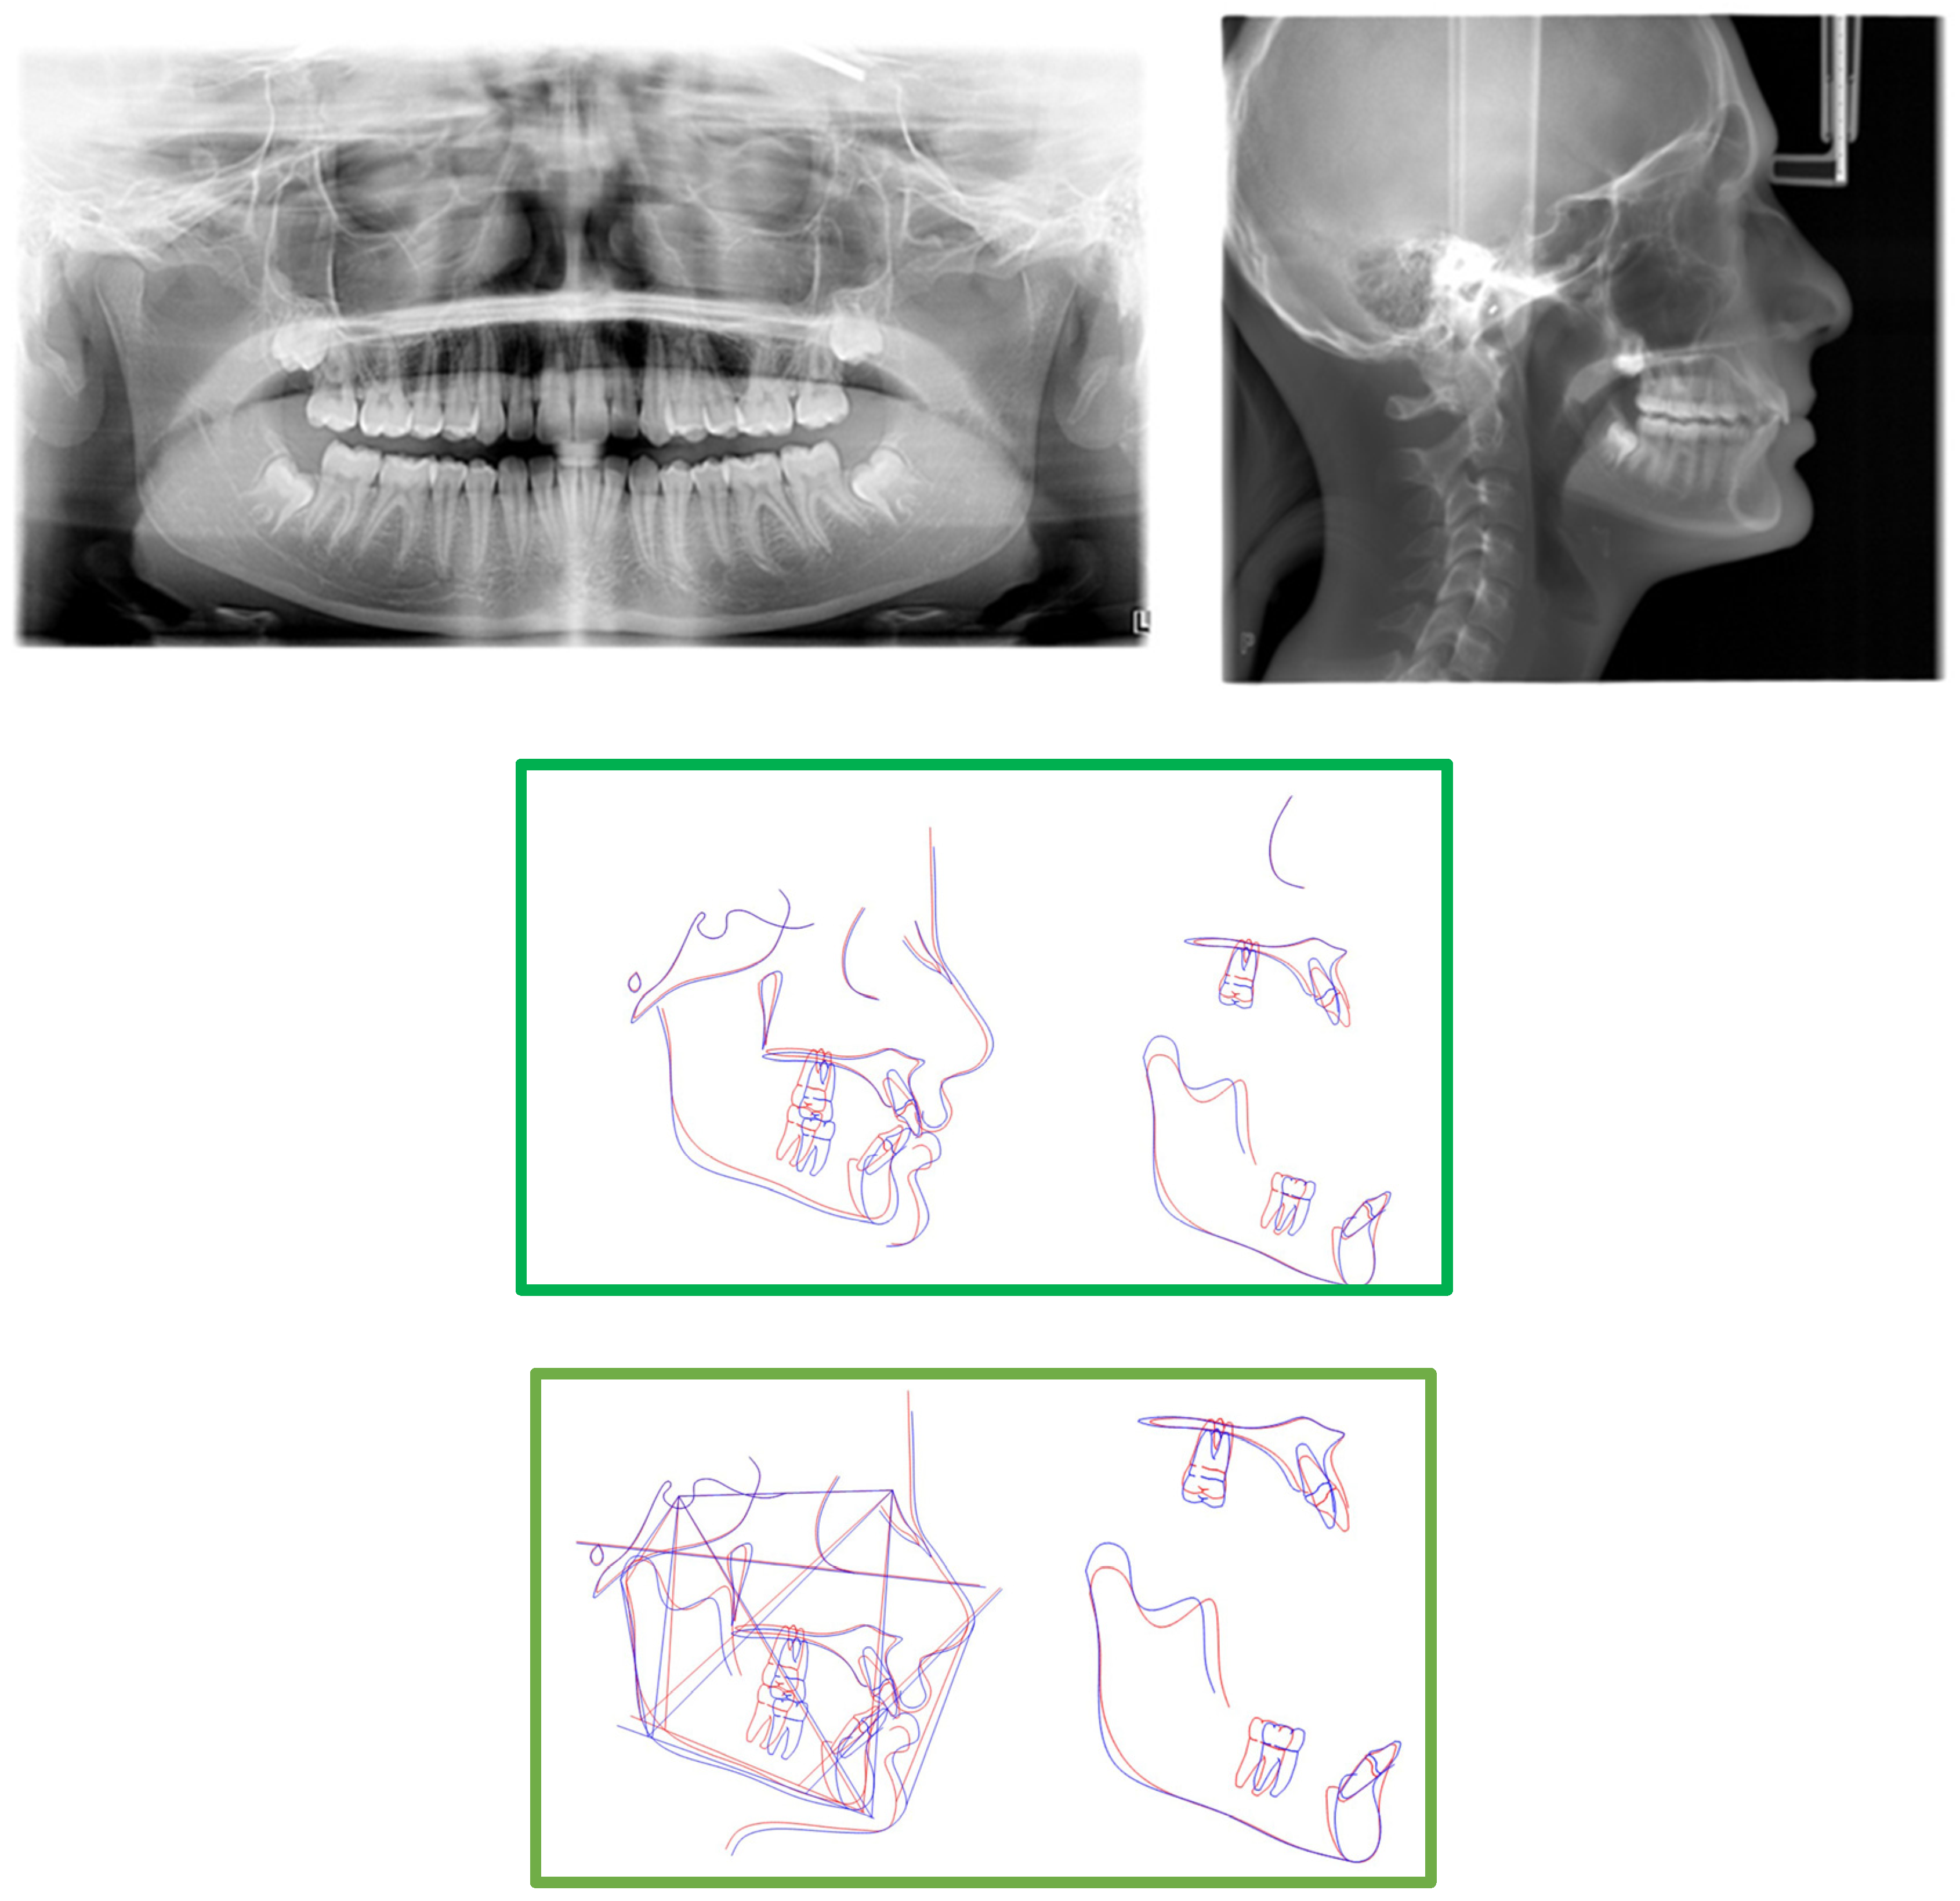

2.3. Treatment Progress

- Surgical exposure of the left mandibular canine using a diode laser (Doctor Smile, Lambda Spa, Brendola, Vi, Italy) for operculectomy and excision of fibromucous tissue. The corticotomy was performed using an ultrasonic piezosurgery system (Mectron Medical Technology, Carasco, Genova, Italy). A bottom (3M Unitek, Monrovia, CA, USA) was placed labially as close as possible to the canine’s coronal tip, combined with a metallic ligature and a cantilever (0.016 × 0.022 TMA, American Orthodontics, Sheboygan, WI, USA) without sutures (Figure 3a,b). The cantilever allowed for distal and buccal traction with light forces (1.7–2.8 ounces). A lingual arch was soldered (passive only on 31–32);

- Fixed multibrackets appliance (American Orthodontics Corp., Sheboygan, WI, USA, MBT prescription) were placed in the upper arch with 0.014 NiTi wire, bent back for controlling anchorage;

- After one month, a 0.016 NiTi wire was inserted in the upper arch;

- Fixed multibracket appliances were placed in the lower arch with a 0.014 NiTi wire, starting vertical traction of the canine. A bent back was used for controlling anchorage;

- After two months, the inferior left canine achieved a vertical position and reached its position in the arch. The bracket was replaced to adjust its axial inclination, and then a 0.016 NiTi wire was inserted;

- Before using stainless steel wire, a ligature from 16 to 26 and 36 to 46 for controlling anchorage was placed;

- 0.016 × 0.022 stainless steel wire was inserted in the upper and lower arches;

- 0.019 × 0.025 stainless steel wire was inserted in the upper and lower arches;

- Reverse Pin System” was placed on 13 and 23 to initiate class II biomechanics. Class II elastics (upper canines and first inferior molars) 3/8 4.5 ounces were used (Figure 3c). Class II elastics were used for 18 h every day;

- One year later, class I occlusion was achieved, and the class II elastics were used only during nighttime;

- Two years later, the appliance was deboned, and positioner retainers were given to the patient with the prescription to wear them every night.

| Measurement | Initial | Final | Norm |

|---|---|---|---|

| S^N^A | 85.2° | 85.5° | 81° |

| S^N^B | 81.3° | 81.8° | 79° |

| A^N^B | 4.2° | 3.7 | 2° |

| SN^Pog | 82.5° | 84.3° | 80° |

| S | 107.7° | 122.8° | 123° ± 5° |

| AR | 168.2° | 143° | 143° ± 6° |

| Go | 106.2 | 111.4° | 130° ± 7° |

| Upper gonial angle | 43.2° | 50° | 52°–55° |

| Lower gonial angle | 63° | 61.3° | 70°–75° |

| N^S^Ar^Go^Gn | 382.1° | 377.2° | 396° |

| Sn/Go-Me | 22.2° | 17.1° | 32° |

| SN | 67.6 mm | 69.7 mm | 71 mm |

| GoMe | 72.3 mm | 78.3 mm | 71 mm |

| S-Ar | 41.3 mm | 32.6 mm | 32 mm |

| Ar-Go | 33.1 mm | 53.8 mm | 44 mm |

| Dentoalveolar component | |||

| UI^SN | 116.15° | 113.37° | 102° ± 2° |

| LI^GOME | 109.72° | 114.5° | 90° ± 3° |

| Interincisal angle | 111.98° | 115.07° | 135° |